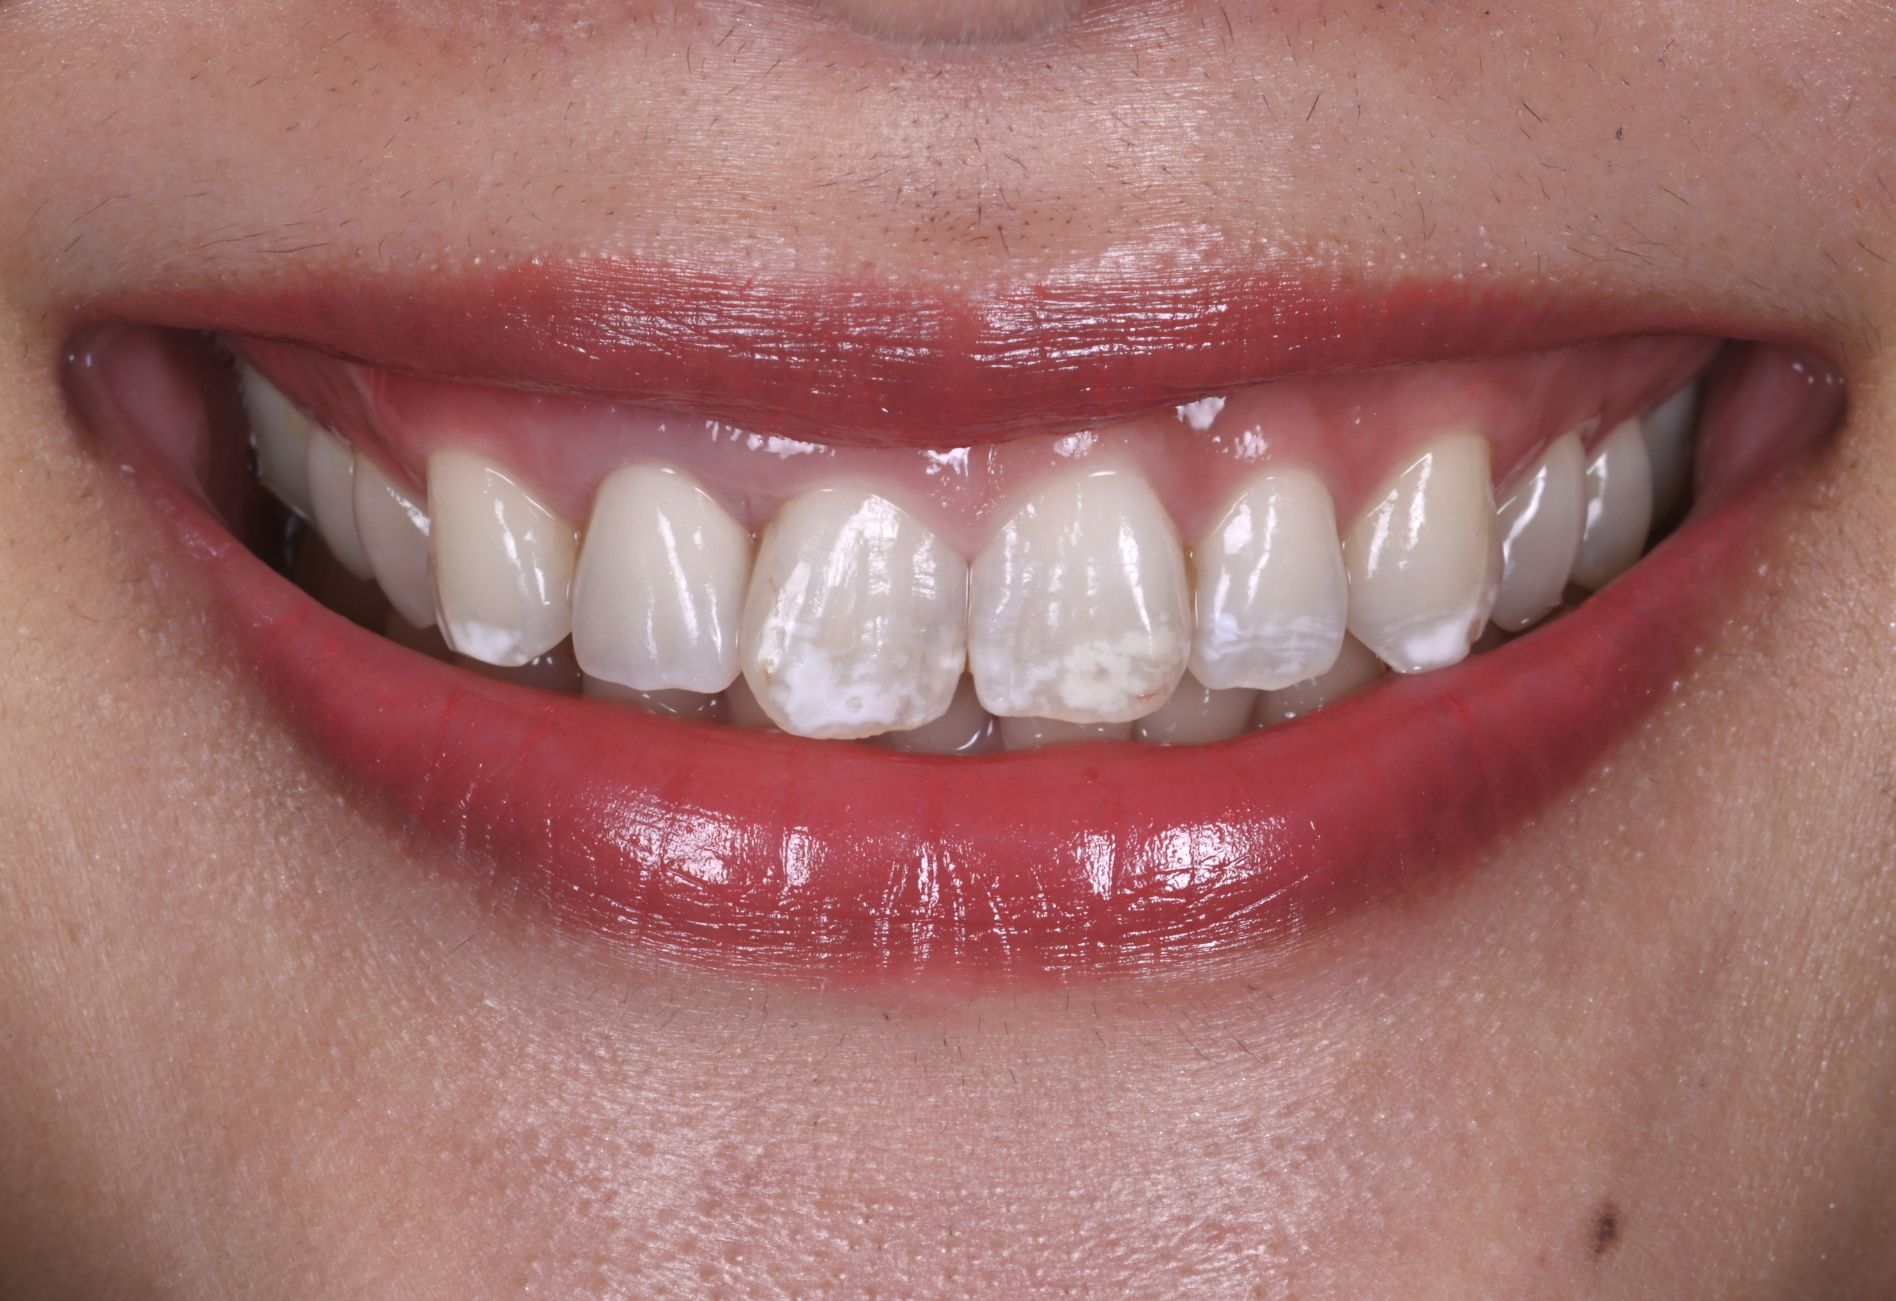

骨造成・歯肉移植を伴うインプラントのやり直し症例

Before

After

年代

40歳代

主訴

前歯5本をやりかえたい。

背景

小学生の頃に転んで前歯を折ってしまってずっと前歯で苦労してきた。

治療

旧インプラント撤去・骨造成・歯肉移植・インプラント治療・セラミック治療

治療期間

1年6ヶ月

治療費用

1,870,000円(税込)